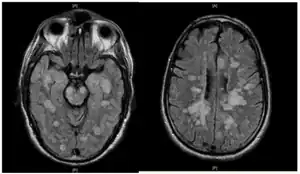

![]() | |

| Fulminating ADEM showing many lesions. The patient survived, but remained in a persistent vegetative state | |